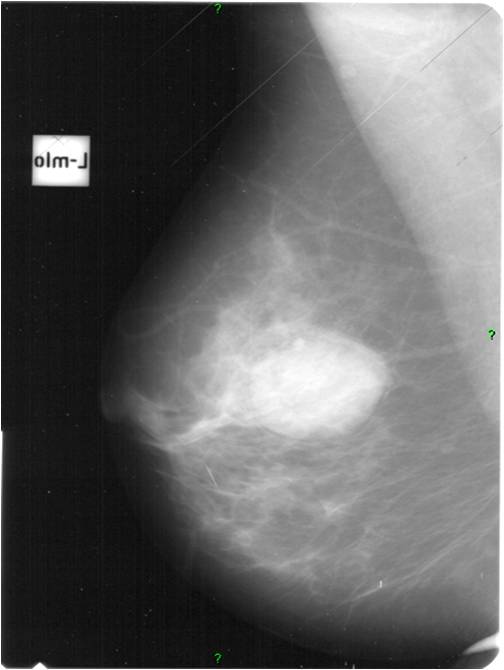

2. Digital mammography has displaced the analogue technic for today almost everywhere: (pictures 1,2,3) phosphorous plate or direct digital methods. For breast imaging the latter is the method of choice. Phases of image production separate. The image is produced on the detectors, but appears on the high resolution monitor and can be stored as a digital data set at various storage mediums (e.g.: CD, hard disk drives).

Image

Picture 1.

Picture 2.

Picture 3.